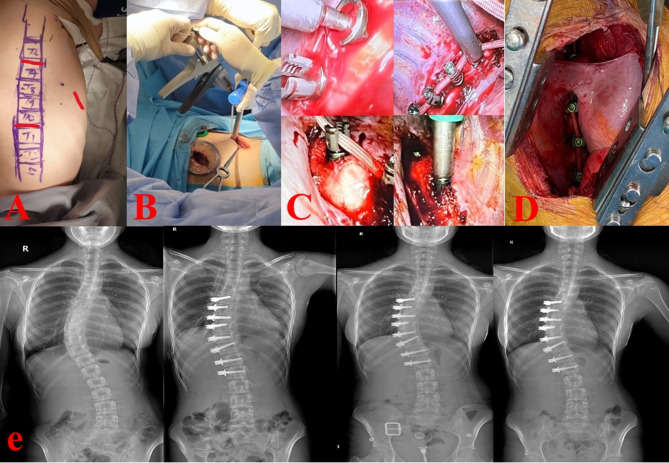

Methods: We have seen a total of 35 cases in our investigation. When doing vertebral body tethering (VBT) in chosen scoliosis patients, thoracoscopy and thoracotomy have been the favored methods. On the other hand, alternative circumstances have favored the usual thoracotomy method.

Results: We operated on three (8.6%) patients for trauma, six (17.1%) for mass, and 26 (74.2%) for scoliosis. Twenty (57.1%) of the patients operated for scoliosis underwent VBT. In patients undergoing VBT, a greater number of vertebrae were accessed thoracoscopy compared to thoracotomy (p = 0.003). There was no significant difference between the two groups in terms of chest tube follow-up time, length of stay in the intensive care unit, and hospital stay (p = 0.451, p = 0.403, p = 0.125).

Conclusion: Our investigation demonstrated that the thoracoscopy is capable of intervening with a greater number of vertebrae compared to thoracotomy. Thoracic surgeons primarily focus their research on masses and trauma related to spinal surgery. Our study's large patient population with scoliosis surgery adds to the existing body of knowledge in the field of thoracic surgery. This study is significant as it is the second in the existing literature to document the experiences of thoracic surgeons from Turkey use of VBT.